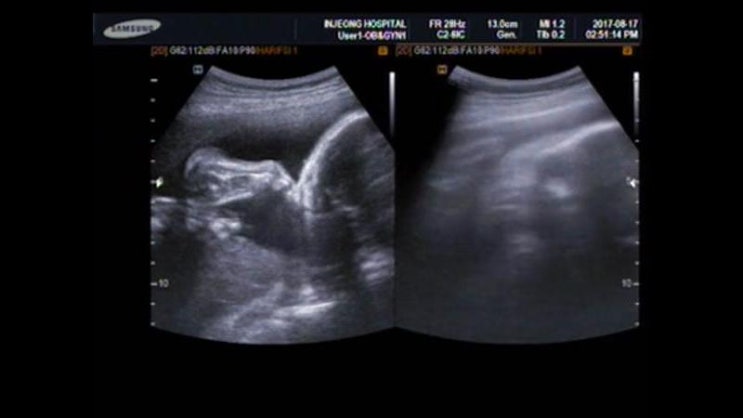

꼬기 입체초음파 (임신 26주 6일, 임신 7개월) 누구를 더 닮았나 ㅎㅎ

+ 꼬기 얼굴 보던 날 + 임신 26주 6일, 임신 7개월 입체 초음파 + 임당 검사 꼬기에 대한 기록은 밀...